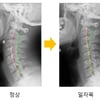

일자목

[김태겸의 척추이야기] 경추 통증, 일자목 증후군